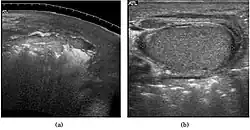

The incidence of infertility is decreased if surgical orchiopexy is carried out before the 1–3 years but the risk of malignancy does not change. Because of the superficial location of the inguinal canal in children, sonography of undescended testes should be performed with a high frequency transducer. At ultrasound, the undescended testis usually appears small, less echogenic than the contralateral normal testis and usually located in the inguinal region [Fig. 29]. With color Doppler, the vascularity of the undescended testis is poor.

Fig. 29. Undescended testis. (a) Normal testis in the scrotum. (b) Atrophic and decreased echogenicity of the contralateral testis of the same patient seen in the inguinal region.